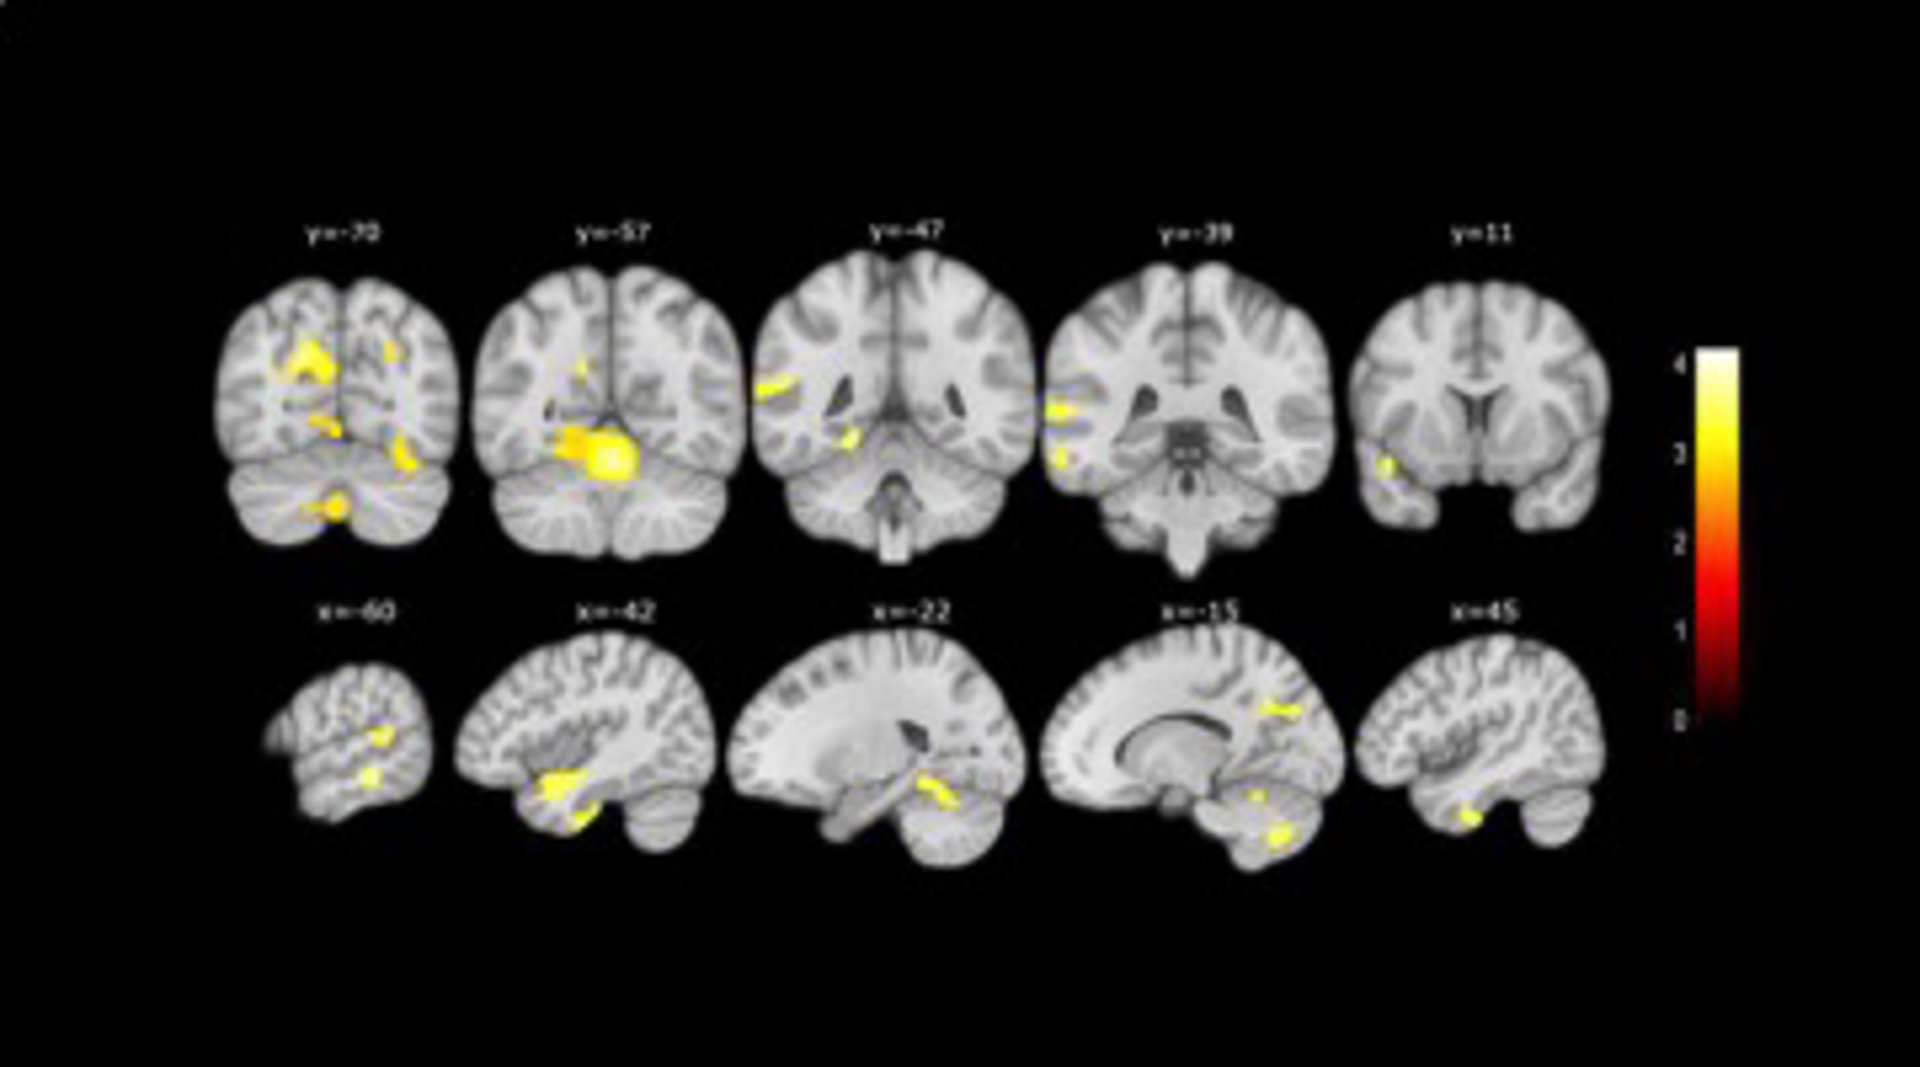

A més, grcies a la ressonncia magntica realitzada a un subgrup de participants, els investigadors també van descobrir que les persones que presentaven més de tres característiques associades als problemes de memria presentaven una atrfia cerebral superior que els altres participants amb menys característiques associades.

MENYS VOLUM

En concret, van observar menys volum en les rees cerebrals que s'afecten en la malaltia de l'Alzheimer, com són l'hipocamp, el lbul temporal, el cerebel i el precúneus.